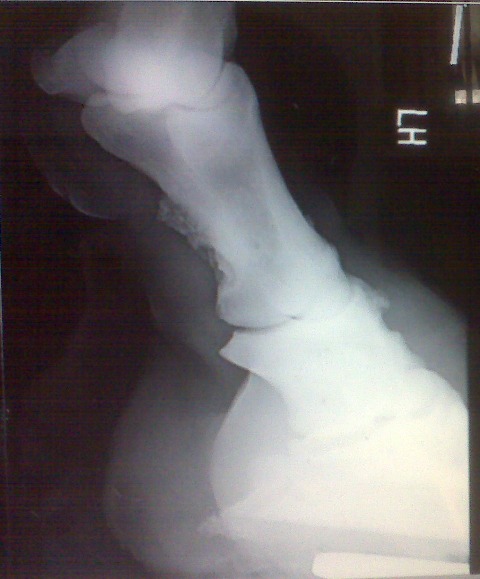

Posted on Sunday, Jun 27, 2010 - 10:00 am: Here are his x-rays that were taken 9/2007. It looks like references I have looked up as ringbone, what do you think?![]() ![]() ![]()

Posted on Tuesday, Jun 29, 2010 - 1:45 pm: Talk about a picture being worth a thousands words! Melissa your horse is not suffering so much from sidebone but has ringbone. This is a periostitis of the bones of the pastern that is spreading into the pastern joint (osteoarthritis) as evidenced by the osteophytes on the distal long pastern bone and proximal short pastern bone. By all means review the article on ringbone at HorseAdvice.com » Diseases of Horses » Lameness » Diseases of the Lower Limb » Ringbone. If you have questions following the article come back you can post them there and I will move this discussion into your post for continuities sake.DrO |